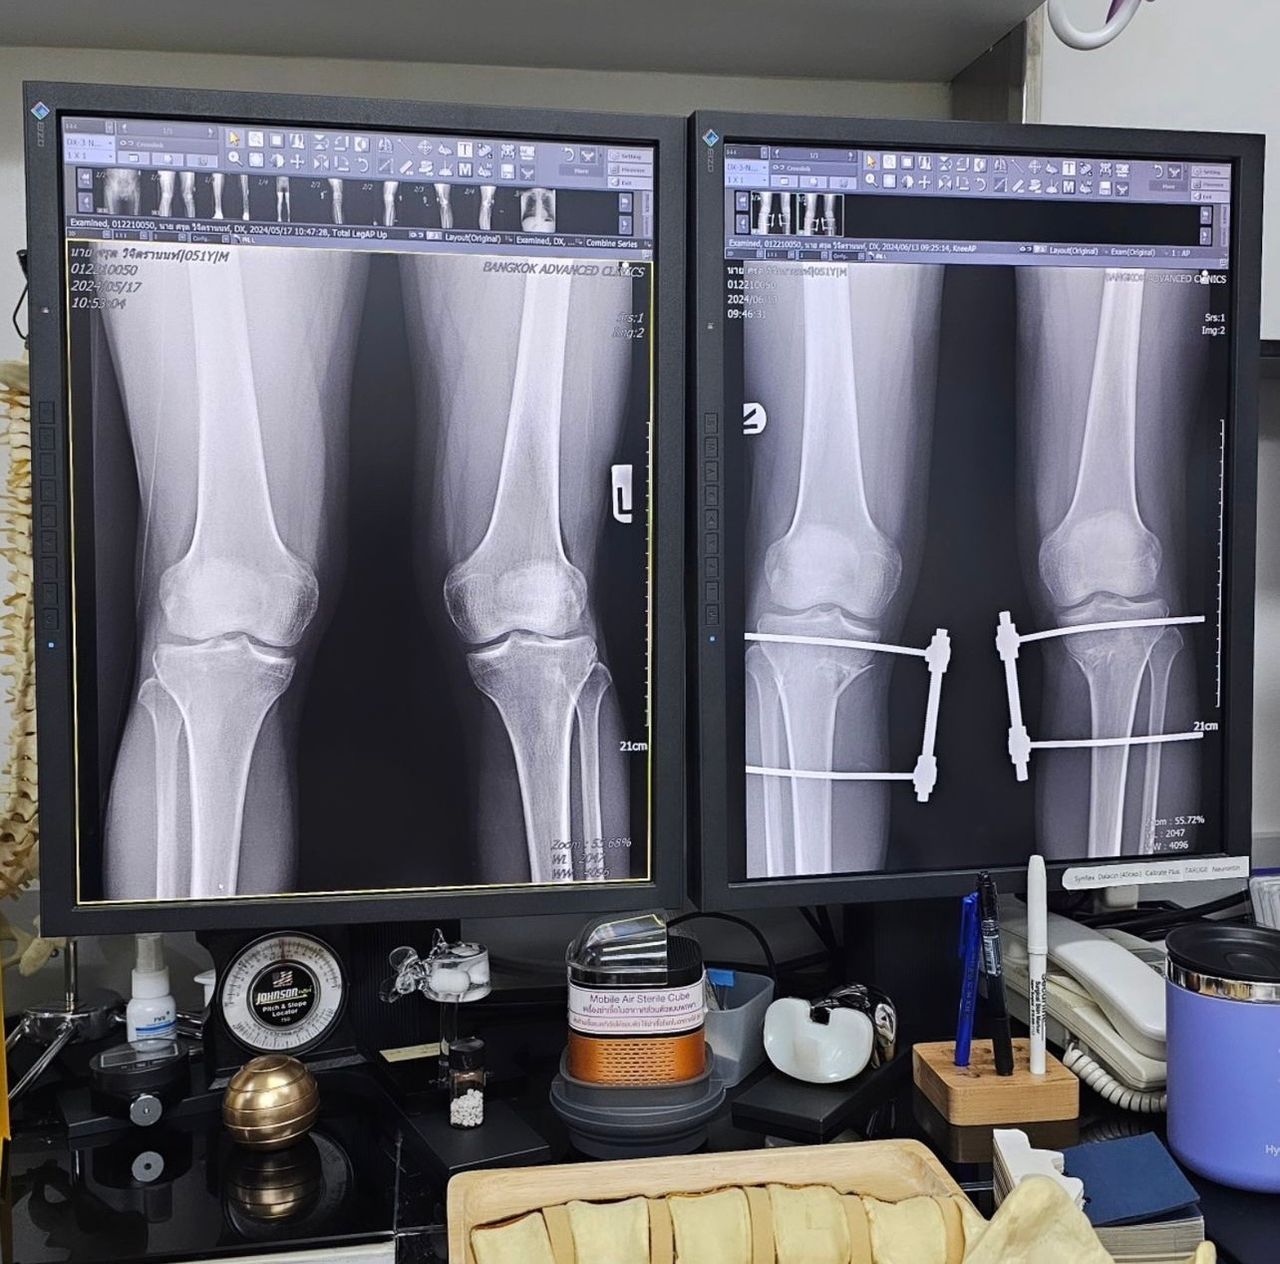

ซึ่งข้อความดังกล่าวระบุว่า "หลายคนอาจสงสัยว่า Knock knee ที่ผมเป็นคืออะไร? วันนี้ผมถ่ายฟิล์ม X-Ray ผมมาให้ดูนะครับจะได้เห็นภาพชัดๆกันไปเลย วันนี้ผมไป follow up กับคุณหมอมา // ขาข้างขวาวันนี้ทำการปรับองศาใหม่อีก 2 องศา ครับ ตอนนี้ทุกอย่างอยู่ในองศาที่ดีและถูกต้องแล้ว จากนี้ก็ไปพบคุณหมอทุกอาทิตย์จนกว่าจะถอดอุปกรณ์ออกครับ

ในฟิล์ม X-Ray ให้สังเกตที่แนวต้นขากับหน้าแข้งของผมก่อนผ่ากับหลังผ่าดูนะครับ ก่อนผ่าเข่าบีบเข้าหากันเยอะอยู่ครับ(ขาฉิ่ง) หลังผ่ารูปร่างของขาโดยรวมเปลี่ยนไปค่อนข้างเยอะเลยทีเดียวครับ บางทีเรามองด้วยตาเปล่าเราแทบไม่รู้สึกนะครับ แต่ในฟิล์มนี่ชัดเลยครับผม